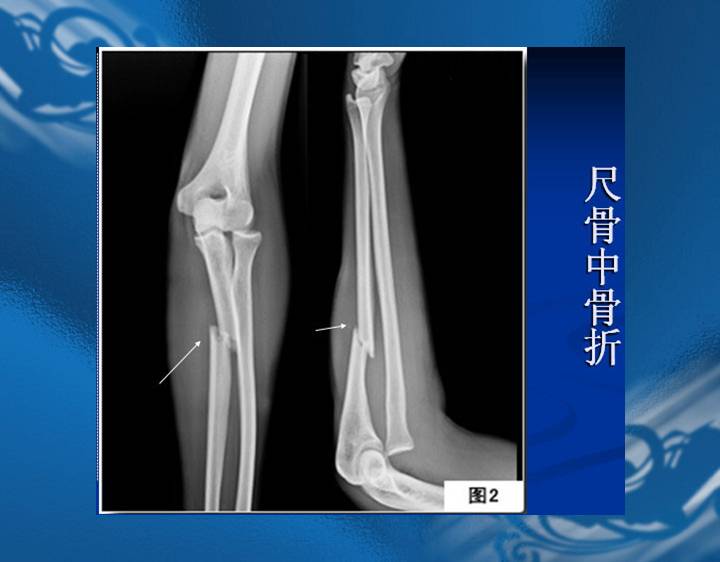

执业医师资格考试“实践技能”影像学辅导资料